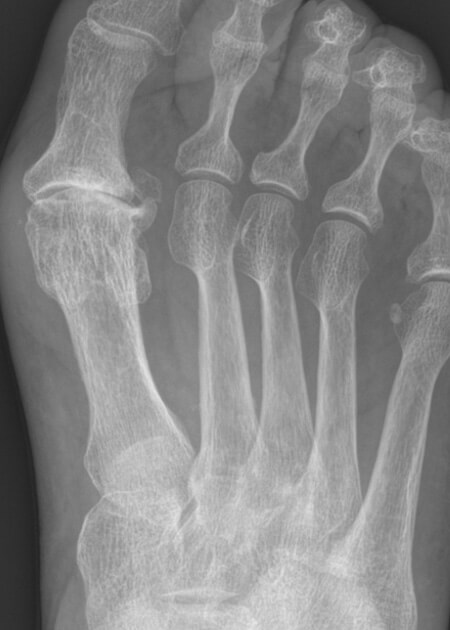

Radiografía de hallux rigidus en pie derecho.